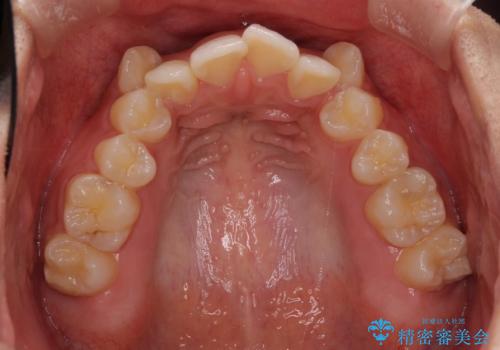

- 顕著な八重歯が気になるとのことで来院された患者様です。

インビザラインでの治療を希望されましたが、インビザライン単独では困難と判断されたため、補助装置や一部ワイヤー装置を用いて行うこととしました。

叢生が強いため、上下左右第一小臼歯4本を抜歯することとしました。

ワイヤー装置を用いた場合、一般的には2年程度で終了することを考えると、「移動量が多くなると治療期間が長くなる」というインビザライン矯正の最大の弱点が現れた治療となりました。